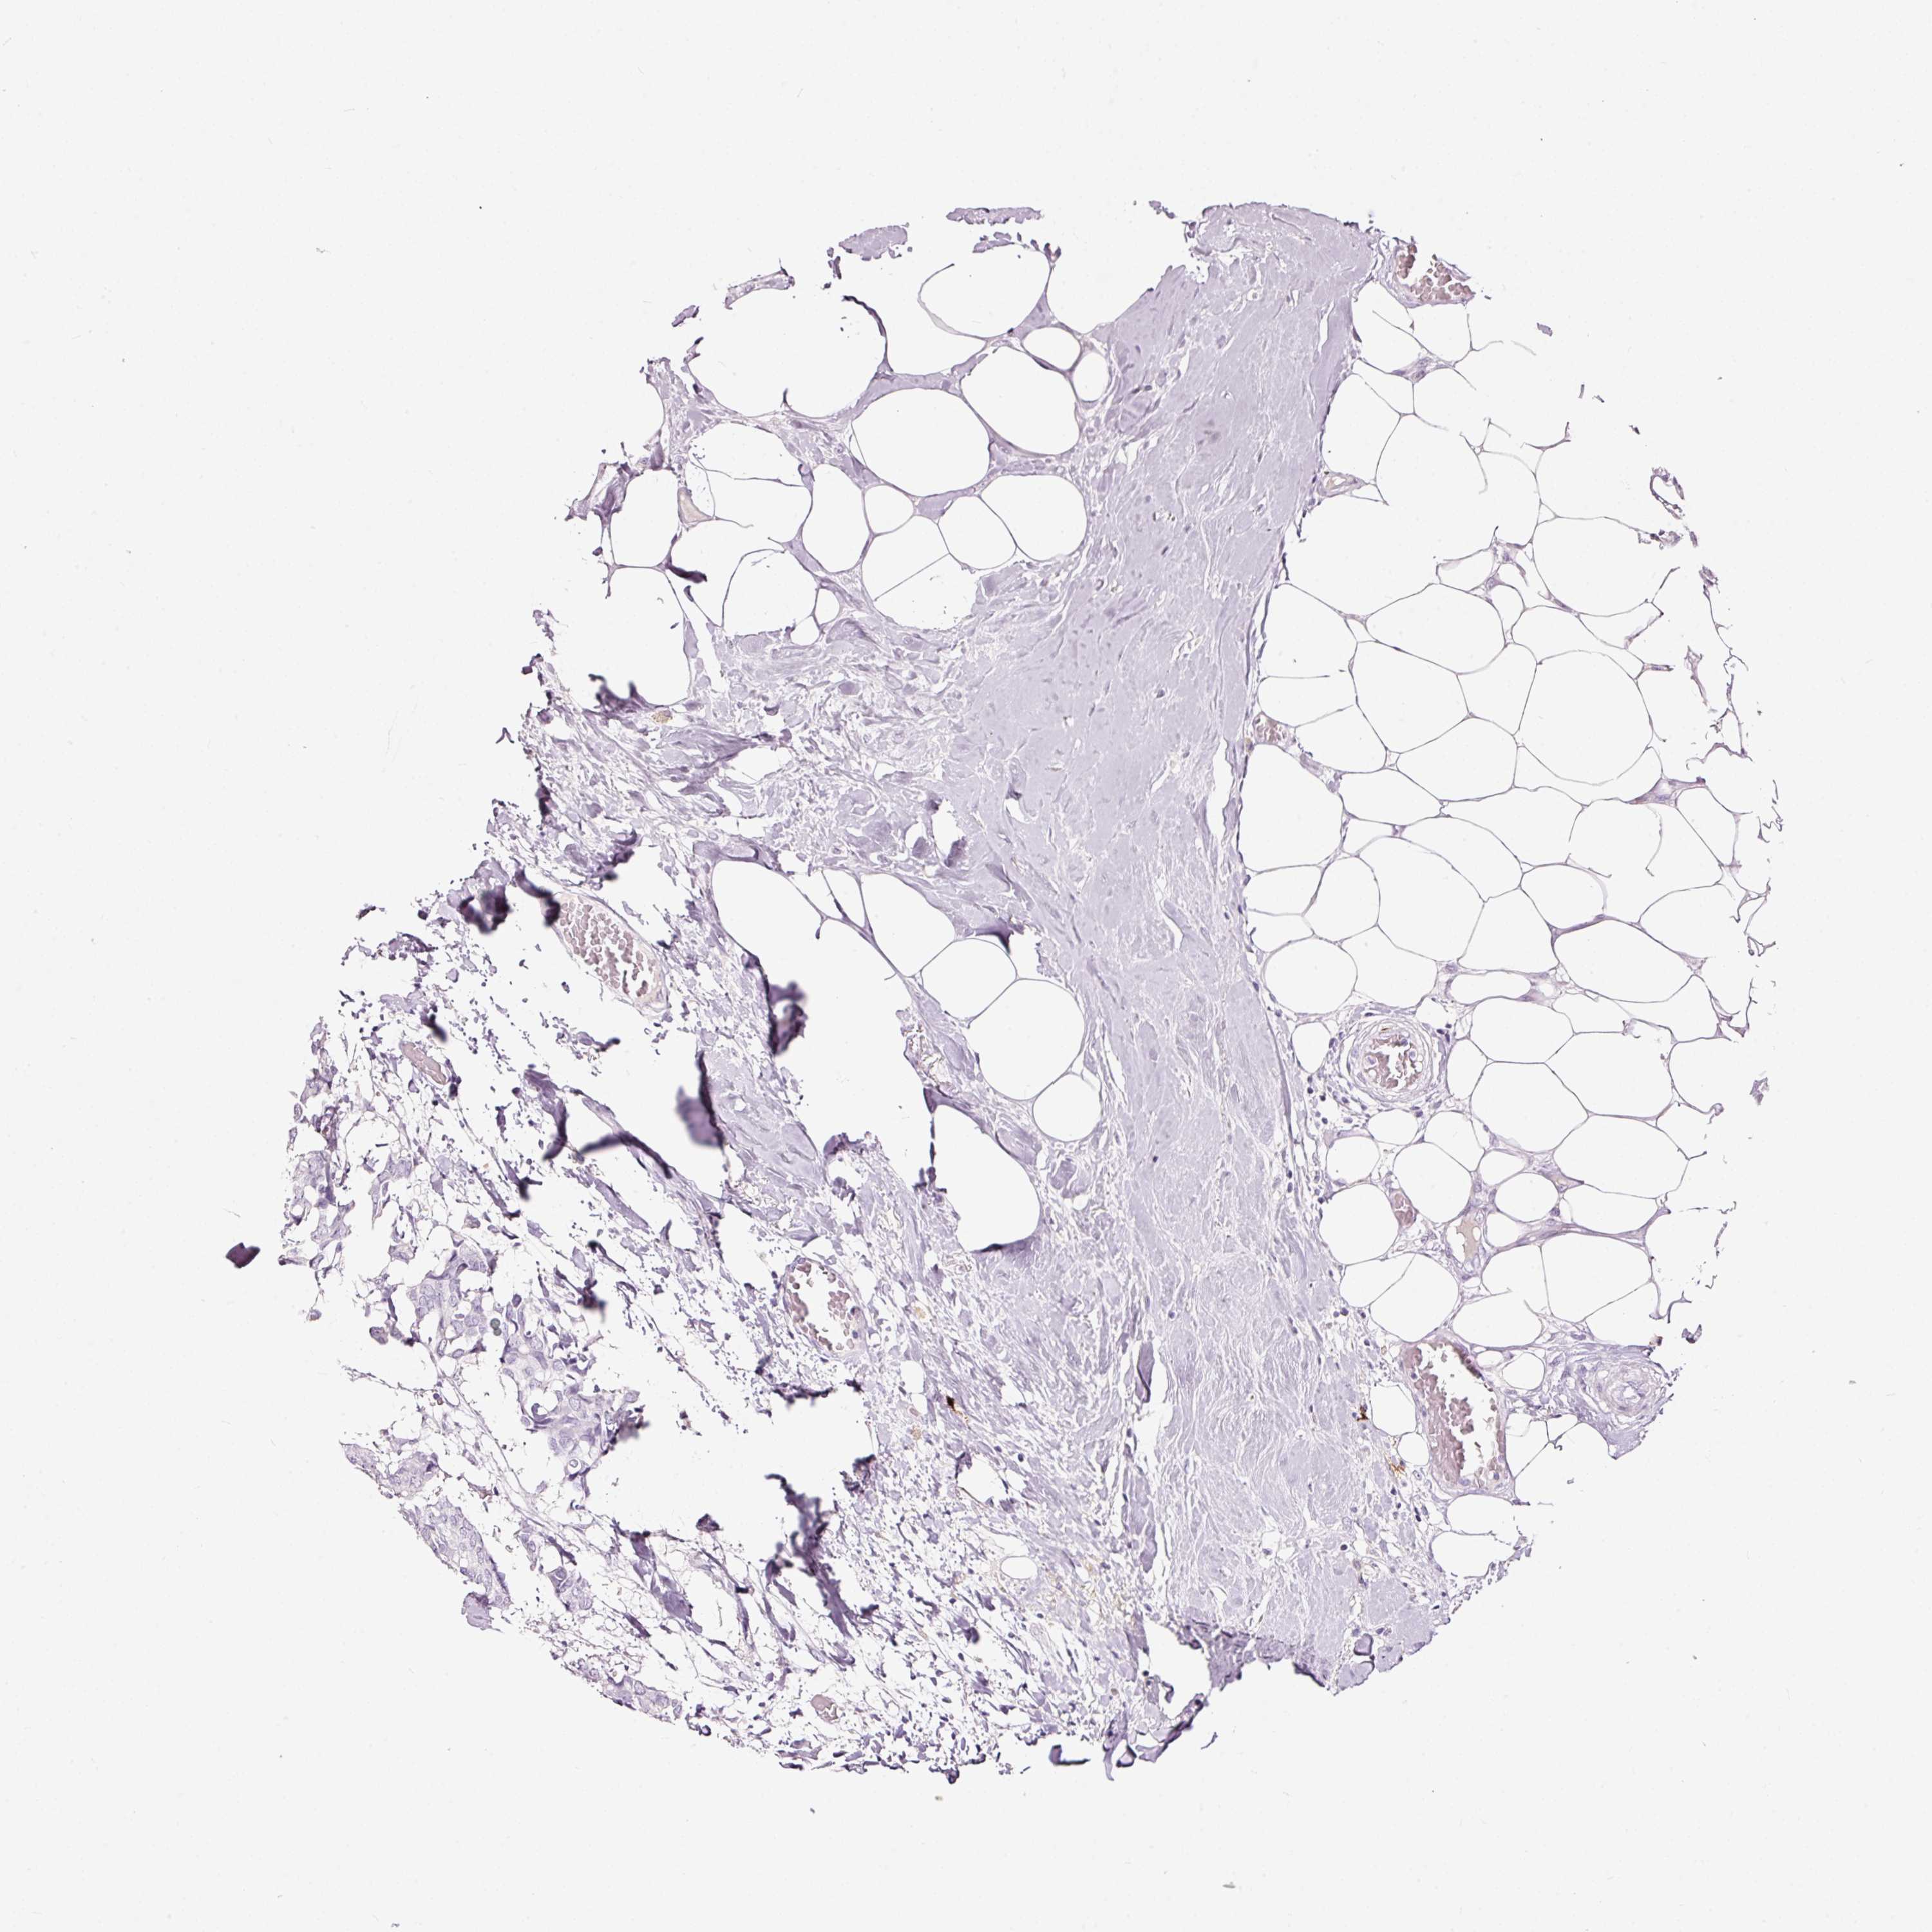

BRCA TCGA BRCA VALIDATION PROTEIN EXPRESSION

Breast cancer

Human cancer